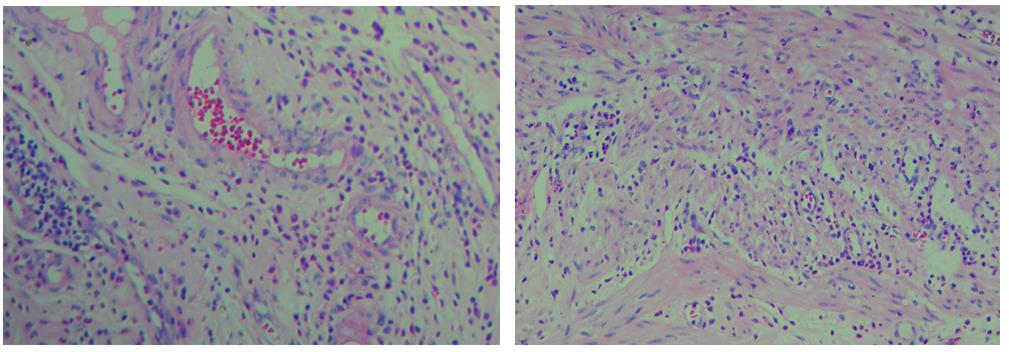

3、色彩鮮艷,核漿紅藍對比鮮明,染色效果持久穩定,胞核結構清晰

細胞中的細胞核由帶負電荷的酸性物質組成,與帶正電荷的堿性染料蘇木素的氧化物三氧化蘇木紅有較強的親和力;而細胞漿則相反,因含有帶正電荷的堿性物質而與帶負電的酸性染料曙紅Y的親和力較強;細胞或組織切片經HE染色后,細胞核被染成藍紫色,細胞漿、紅細胞、肌纖維、膠原纖維、結締組織、嗜伊紅顆粒等被染成不同程度的紅色、粉紅色或橙紅色,與藍色的細胞核形成鮮明的對比,因此更易于觀察細胞或組織中正常成份和病變成份的一般形態結構。

【實際染色效果】